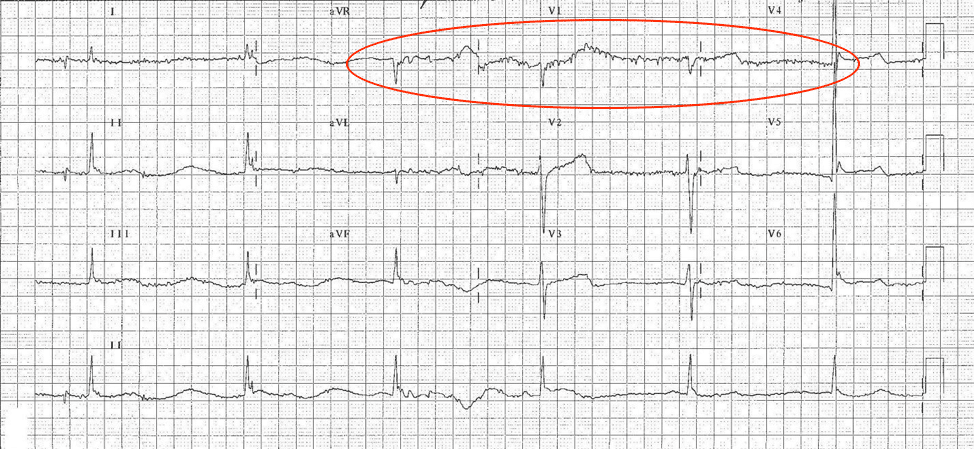

The heart’s electrical activity is sometimes prevented from reaching the ECG electrodes. This interference, called artifact, can hinder the correct recording of actual impulses from the heart. Artifacts can be caused by muscle tremors, shivering, patient movement, loose electrodes, or electrical signals from other devices inside the room (see Figure 2.6).

ECG of Hypothermic Patient